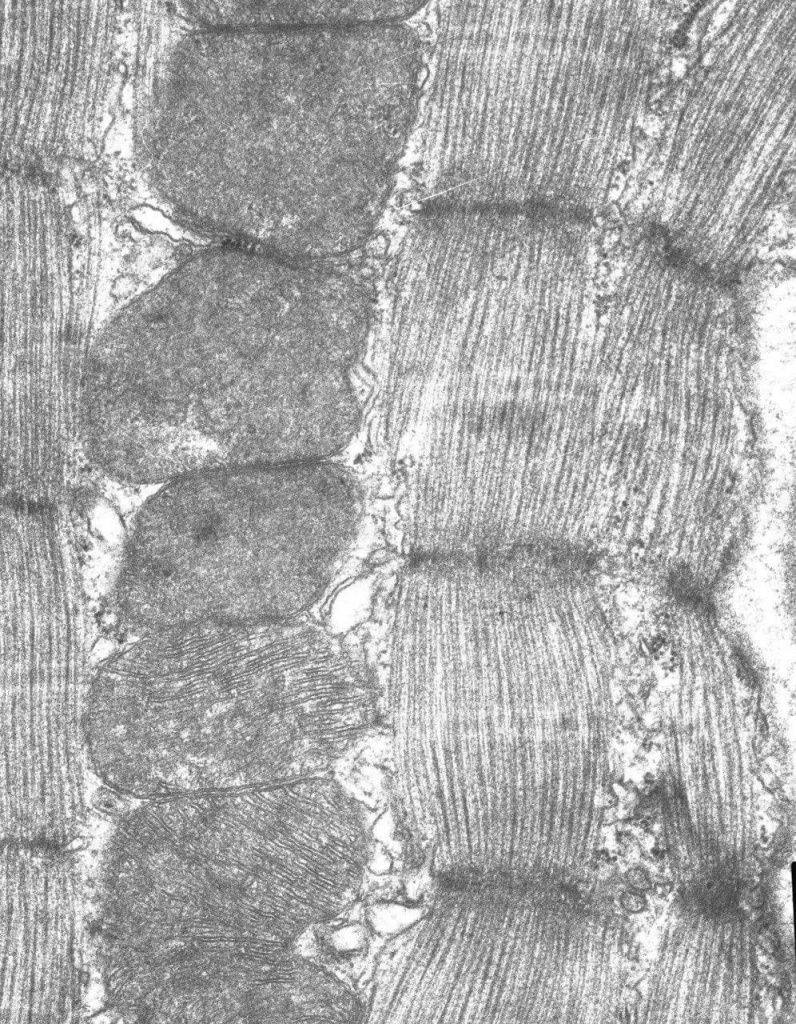

Увидеть важное через микроскоп смогла команда учёных, более 20 лет изучающих митохондрию – важную часть живой клетки организма, которая отвечает за её энергообеспечение.

Подобные исследования проводят учёные во всем мире. В этом году наши специалисты представят к публикации сразу несколько научных статей, в которых опишут действие новых лекарственных препаратов, оказывающих благоприятное воздействие на митохондрии.

- В основе многих заболеваний лежит нарушение функционирования митохондрий. Мы изучаем то, как можно скорректировать их работу с помощью лекарственных препаратов нового поколения. Есть подвижки при изучении состояния живого организма при диабете, патологиях сердечной мышцы и скелетной мускулатуры.

В лабораторных условиях, где испытуемыми являются мыши, мы испытали несколько новых перспективных препаратов, который улучшили функционирование митохондрий при этих патологиях. Препараты пока не используется в лечении человека, а только испытываются, проверяются и их побочные эффекты. Но важно, что с их помощью происходит коррекция патологий, улучшается состояние испытуемых животных, а в будущем это может помочь и людям с подобными заболеваниями жить дольше и, самое главное, улучшит качество их жизни , - рассказал заместитель директора по НИД, доцент кафедры биохимии, клеточной биологии и микробиологии Михаил Дубинин.